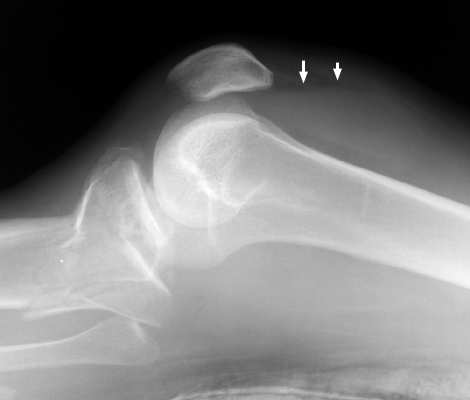

Fat fluid interface seen on the multiple lateral radiographs of the knee secondary to lipohemarthrosis. The fat-blood interface (FBI) is a very suggestive sign of underlying fracture extending into the joint. If no fracture is readily identified, diligent search should be undertaken.

Cross table lateral knee - Click on the image for a larger versionACross table lateral - Click on the image for a larger versionB